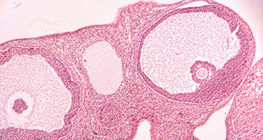

5 дахин томруулсан